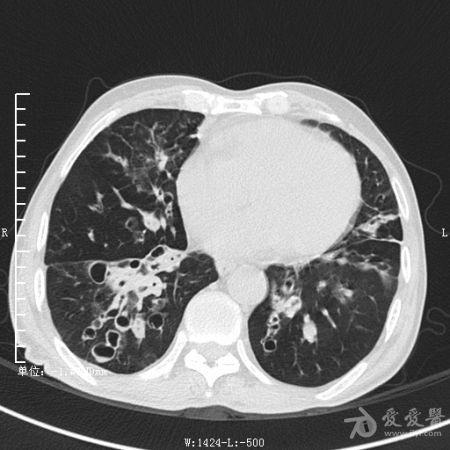

典型支气管扩张及肺水肿CT片

典型支气管扩张肺水肿